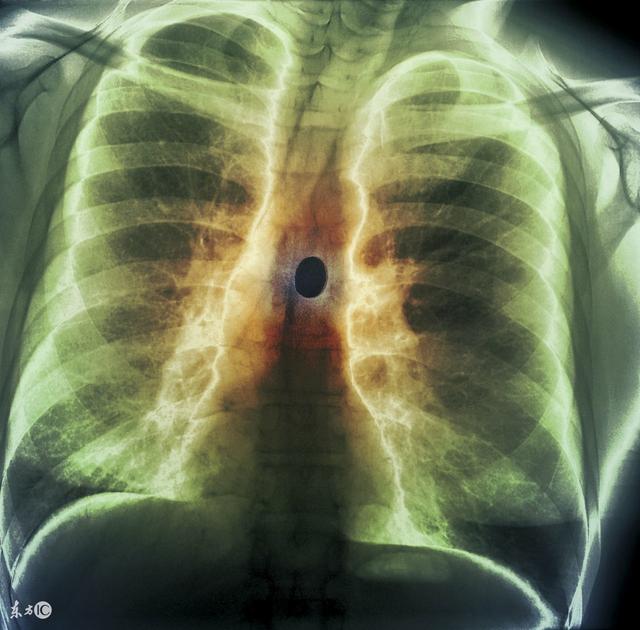

过敏性鼻炎是常见的耳鼻咽喉科疾病,也是呼吸道的变应性疾病,发病率有全球性逐年增加的趋势。儿童的发病率在10%~40%左右。过敏性鼻炎本身虽不是严重疾病, 但可影响孩子的睡眠、学习和文体活动、并可诱发或合并哮喘、鼻窦炎、中耳炎等。因此,变应性鼻炎的危害性还是很严重的。 然而在生活中儿童的过敏性鼻炎的症状与感冒非常相似,常常发生误诊。正确区分二者对过敏性鼻炎的诊治显得尤为重要。

过敏性鼻炎是指我们中的易感人群接触引起过敏的物质后发生的以鼻部症状(鼻痒、阵发性喷嚏、大量水样鼻涕和鼻塞等)为主要表现的变态反应性疾病。可分为常年性过敏性鼻炎和季节性过敏性鼻炎,前者主要由各种尘螨、蟑螂、霉菌等引起,常年发病,后者又称为花粉症”,是指患儿接触花粉等致敏原后,引起发病,具有明显的季节性,即每年的特定季节的某种花开放时发病。

过敏性鼻炎患儿的鼻子的症状非常明显和突出。典型的症状包括打喷嚏、鼻子痒、流清水样鼻涕,鼻子堵塞。打喷嚏可以很多且剧烈,呈阵发性发作,常连续打几个、十几个或者数十个不等。之后就会流大量的清水样鼻涕,随之鼻子堵塞就很严重。此时也可以出现眼睛痒,结膜红肿的表现。严重的患儿可以出现特有的三个特征面容:①过敏性黑眼圈:由于下眼睑水肿而出现下睑暗影;②过敏性皱褶:由于经常揉搓而在鼻背下方出现横行皱纹;③过敏性敬礼:为减轻鼻痒和使鼻腔通畅而用手掌向上揉鼻。